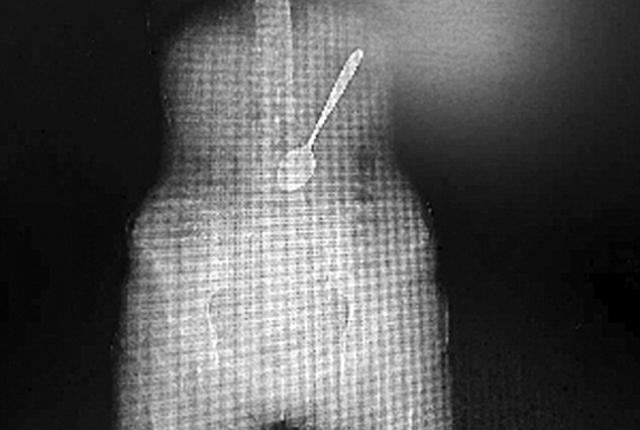

Μία 27χρονη γυναίκα από την Κίνα πήγε στο νοσοκομείο προκειμένου οι γιατροί να της αφαιρέσουν ένα κουτάλι που είχε καταπιεί τρώγοντας ζυμαρικά.

Αρχικά δεν την πίστεψαν μέχρι που της έκαναν ακτινογραφία και εντόπισαν το σκεύος μέσα στο στομάχι της.

Στη νεαρή γυναίκα με το όνομα Γουάνγκ έγινε ολική αναισθησία ενώ οι γιατροί προσπάθησαν να αφαιρέσουν το κουτάλι ενδοσκοπικά.

Το έργο ήταν πιο περίπλοκο από ό, τι αναμενόταν, δεδομένου ότι οι στρογγυλεμένες άκρες του σκεύους δυσκόλευαν τους γιατρούς στο να το πιάσουν.

Επίσης το στομάχι της ήταν γεμάτο με τροφή, η οποία έκανε τον εντοπισμό του κουταλιού ακόμα δυσκολότερη.

Τελικά, η γυναίκα τα κατάφερε.